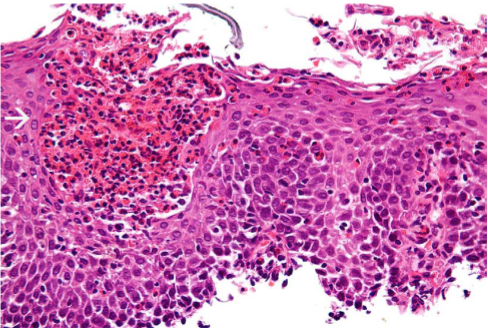

Mild: normal or redness of mucosa due to hyperemia

Severe: Squamous Epithelial hyperplasia + intra-epithelial Eosinophils

Complications of severe long-standing GERD: ulceration with hematemesis or melena, stricture, Barrett’s Esophagus